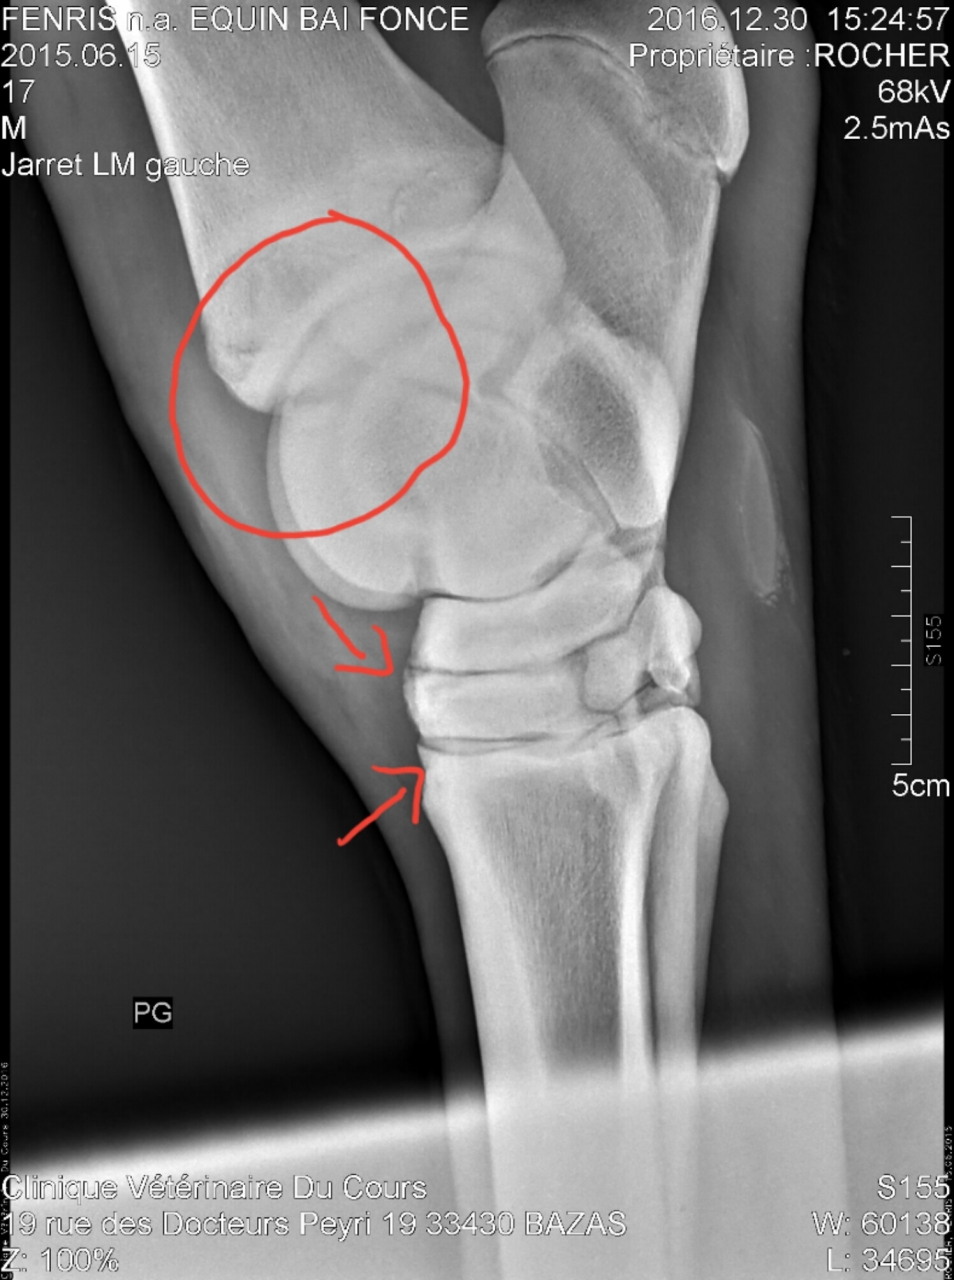

Par moncheval33 : le 31/12/16 à 17:54:20

| Dire merci | J'ai reçu pas mal de clichés, je vous en mets un pour le jarret droit et un pour le jarret gauche de toute façon c'est super dur à interpréter. Jarret D (ce que j'ai entouré en rouge est il me semble ce que la veto interprète comme de l'arthrose, cet sorte de bec) ![]() Jarret G (les flèches montrent ce qui serait de l'arthrose et le cercle situsitue l'endroit où est le fragment mais je ne le trouve plus précisément ... la veto m'a montré tellement de choses c'est difficile de tout mémoriser) ![]() |